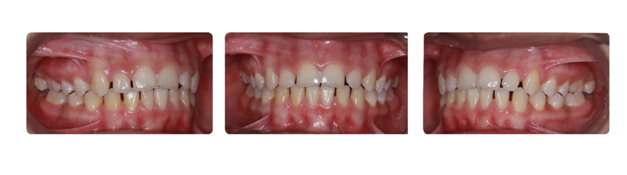

| دندانهای فک بالا و پایین دارای بی نظمی میباشند و با توجه به نبود فضا, بدون کشیدن دندان و توسط سیستم دیمون درمان میشوند: |

![]() |

| درمان با براکتهای دیمون نتیجه بخش است: |